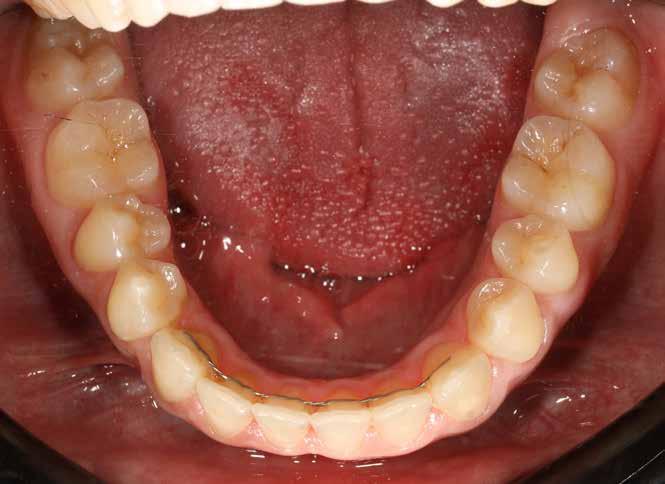

Ebben a cikkben egy 16 éves lánypáciens esetét szeretném bemutatni (1–7. képek)

A Pitts21-es fix készülékes kezelés során a harapásemelőket a felső nagyőrlő fogakra ragasztottuk, hogy a felső molárisok intrúziójával segítsék a harapás zárását (8. kép) Ún. keresztharapásos, majd később normál class 2-es gumihúzással (9–10. képek), továbbá az elülső fogakon alkalmazott ún. Rainbow harapás-záró gumihúzással (11. kép) korrigáltuk a jobb oldali teljes premolárisnyi distal-harapást, valamint az elülső nyitott harapást.

6 hónap után a nyitott harapás már nagyjából összezárásra került (12. kép)! A gumihordás a kezelés teljes hosszában folyamatos, éjjel-nappal, 22-24 órában az étkezések és az utánuk történő fogmosás kivételével.

A fix fogszabályozó készülék mindössze 16 hónapos kezelés után került eltávolításra! Páciensünk legnagyobb örömére állcsontműtét nélkül sikerült mind az arcesztétikai, mind a funkcionális rehabilitáció (13–18. képek)

Minden fogszabályozó kezelés után nagyon fontos a retenció, de ilyen eltérés esetén különösen, mivel a recidíva veszély nyitott harapás esetén a legnagyobb. A fogak és a harapás megtartása fix és kivehető retainer-ekkel történik.

A kivehető helyben-tartók legfontosabb eleme a mindkét fogívet összekötő ún. Splint (19. kép), amely egyrészt saggitálisan tartja a helyén a mandibulát, hogy ne csússzon vissza hátrafelé, másrészt segít a harapás zártan tartásában a növekedés teljes befejeződéséig.